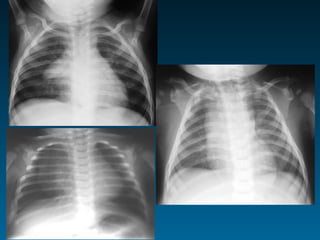

Κυψελιδικού τύπου πύκνωση

Σημείο σιλουέτας